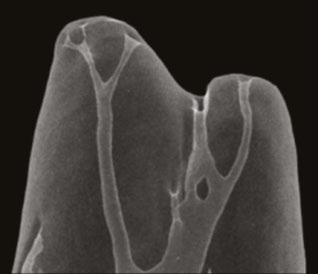

Figure 4A-4C: 4A. Maxillary lateral incisor with an internal resorption at the coronal third. 4B. Mandibular canine with an internal resorption in the middle-apical area. 4C. Mandibular molar with an irregular internal resorption in the coronal portion Figures 5A-5C: